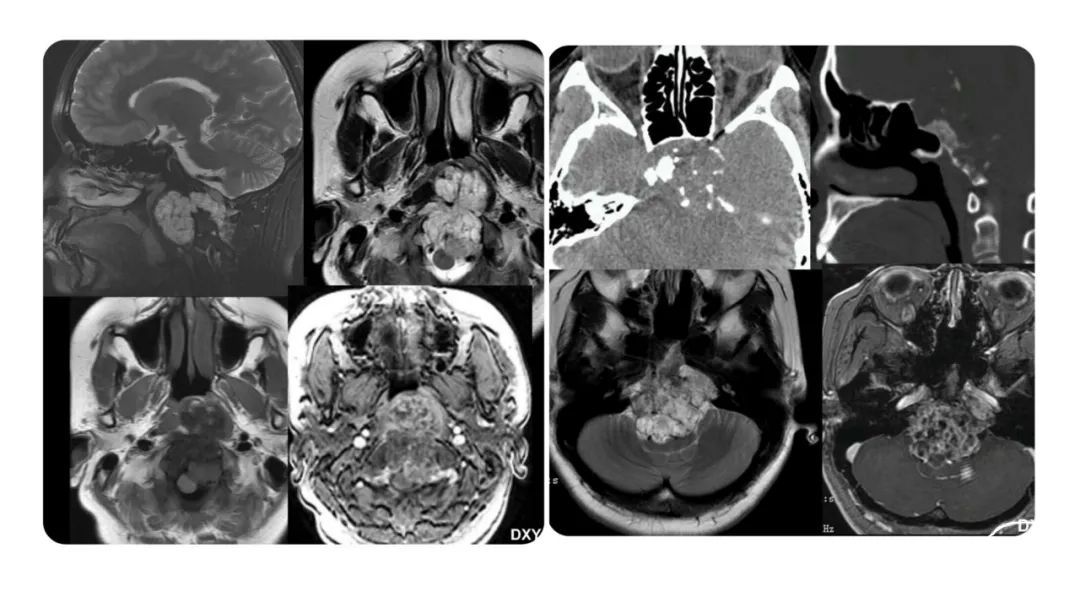

颅脑影像诊断基础知识讲座:颅骨病变